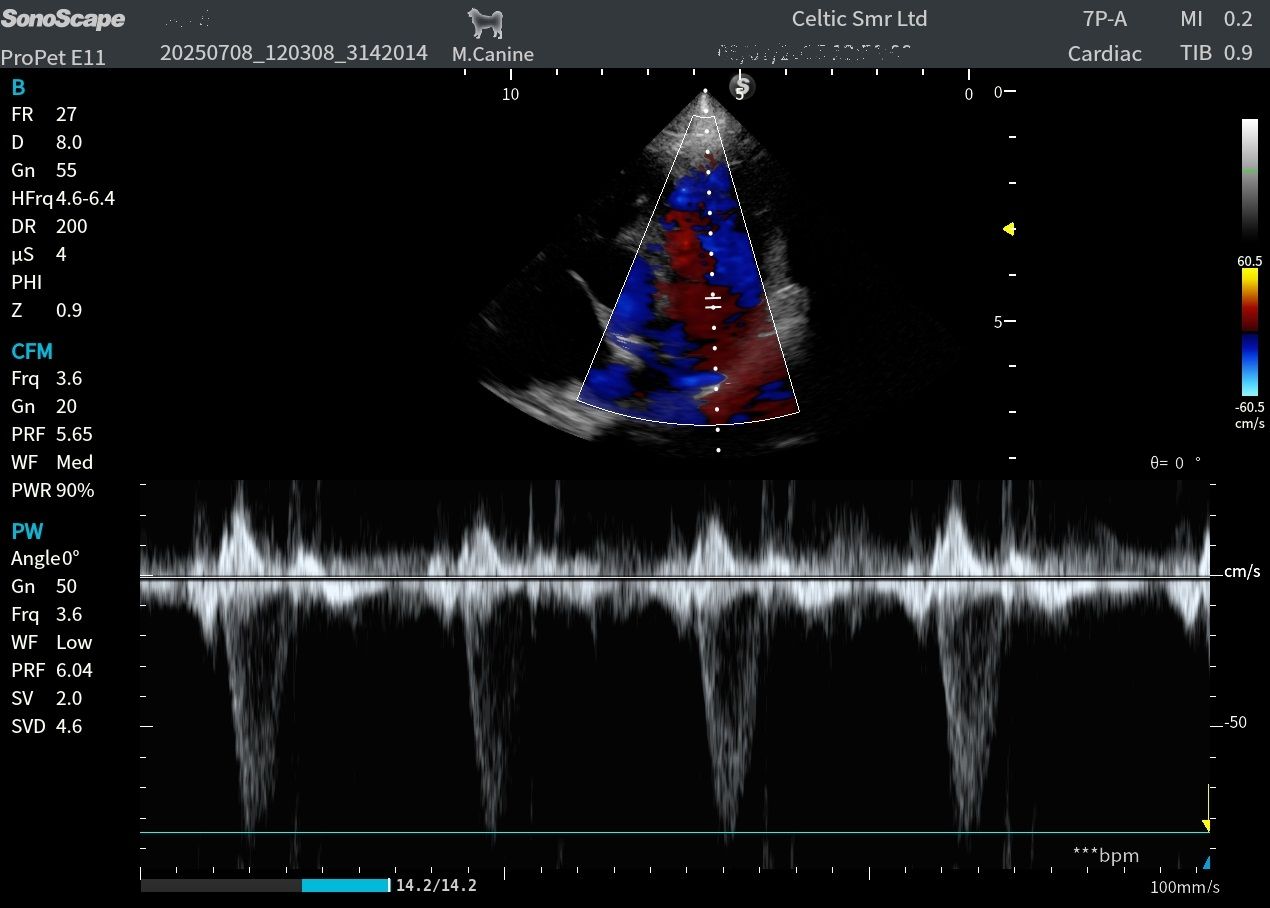

Image quality is one of its absolute highlights. The microconvex and linear probes performed really well for B-mode abdominal scanning, and the microconvex also delivered beautifully clear images in basic cardiac views, so is a great all rounder for the first opinion practice. The phased array probes were equally impressive, producing high-quality heart images suitable for more advanced echo work. For the price point, this machine delivers very good imaging performance.

Images from the ProPet V11